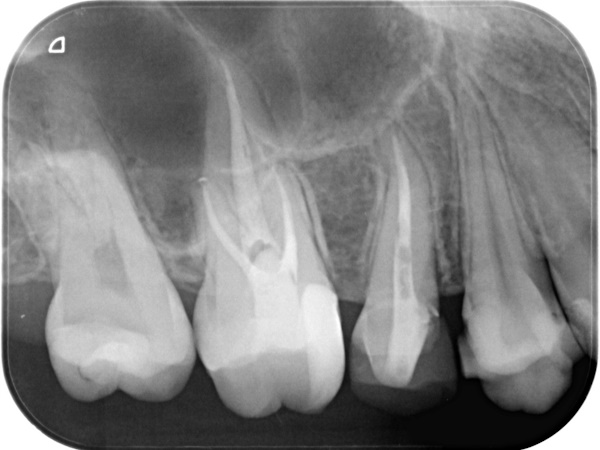

根管治療終了時